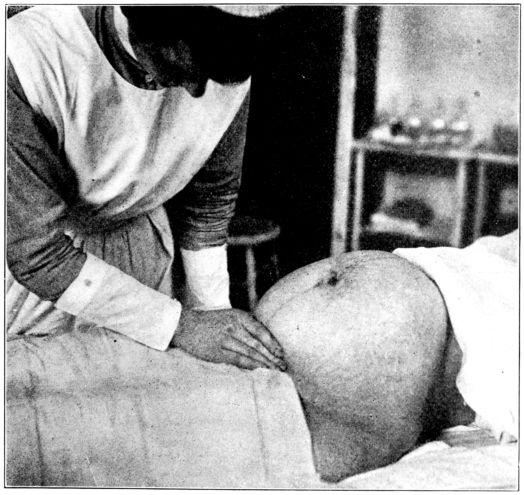

| 57. | First maneuver in abdominal palpation | 225 |

| 58. | Second maneuver in abdominal palpation | 226 |